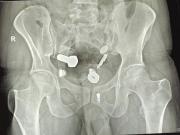

En la capital de Tailandia Pittaya Moolin de 51 años ofrecía y realizaba operaciones de pene.Pero tras varias denuncias la policía descubrió no solo que no se trataba de un médico autorizado sino también que las cirugías eran llevadas a cabo en un lugar insólito por lo... + más